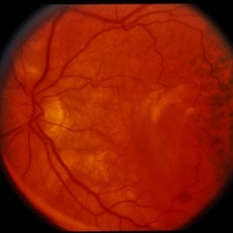

RPE Tear

RPE Tear

Sep 9 2014 by David Callanan, MD

78-year-old male, RPE tear.

Condition/keywords: retinal pigment epithelium